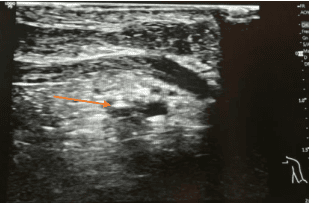

En las siguientes imágenes podemos observar la guía metálica en el interior de la luz del vaso izquierdo y posterior identificación del vaso arterial en la zona axilar mediante el uso del Doppler color. Esta simple comprobación nos permite asegurar la correcta canalización del vaso venoso con datos objetivos.

Mediante estas comprobaciones podemos confirmar el correcto desarrollo de la técnica de canalización para, posteriormente, proceder a la dilatación del punto de inserción y su trayecto, mediante la inserción del microintroductor con cánula pelable a través de la guía, en el interior de la luz del vaso con la máxima seguridad.